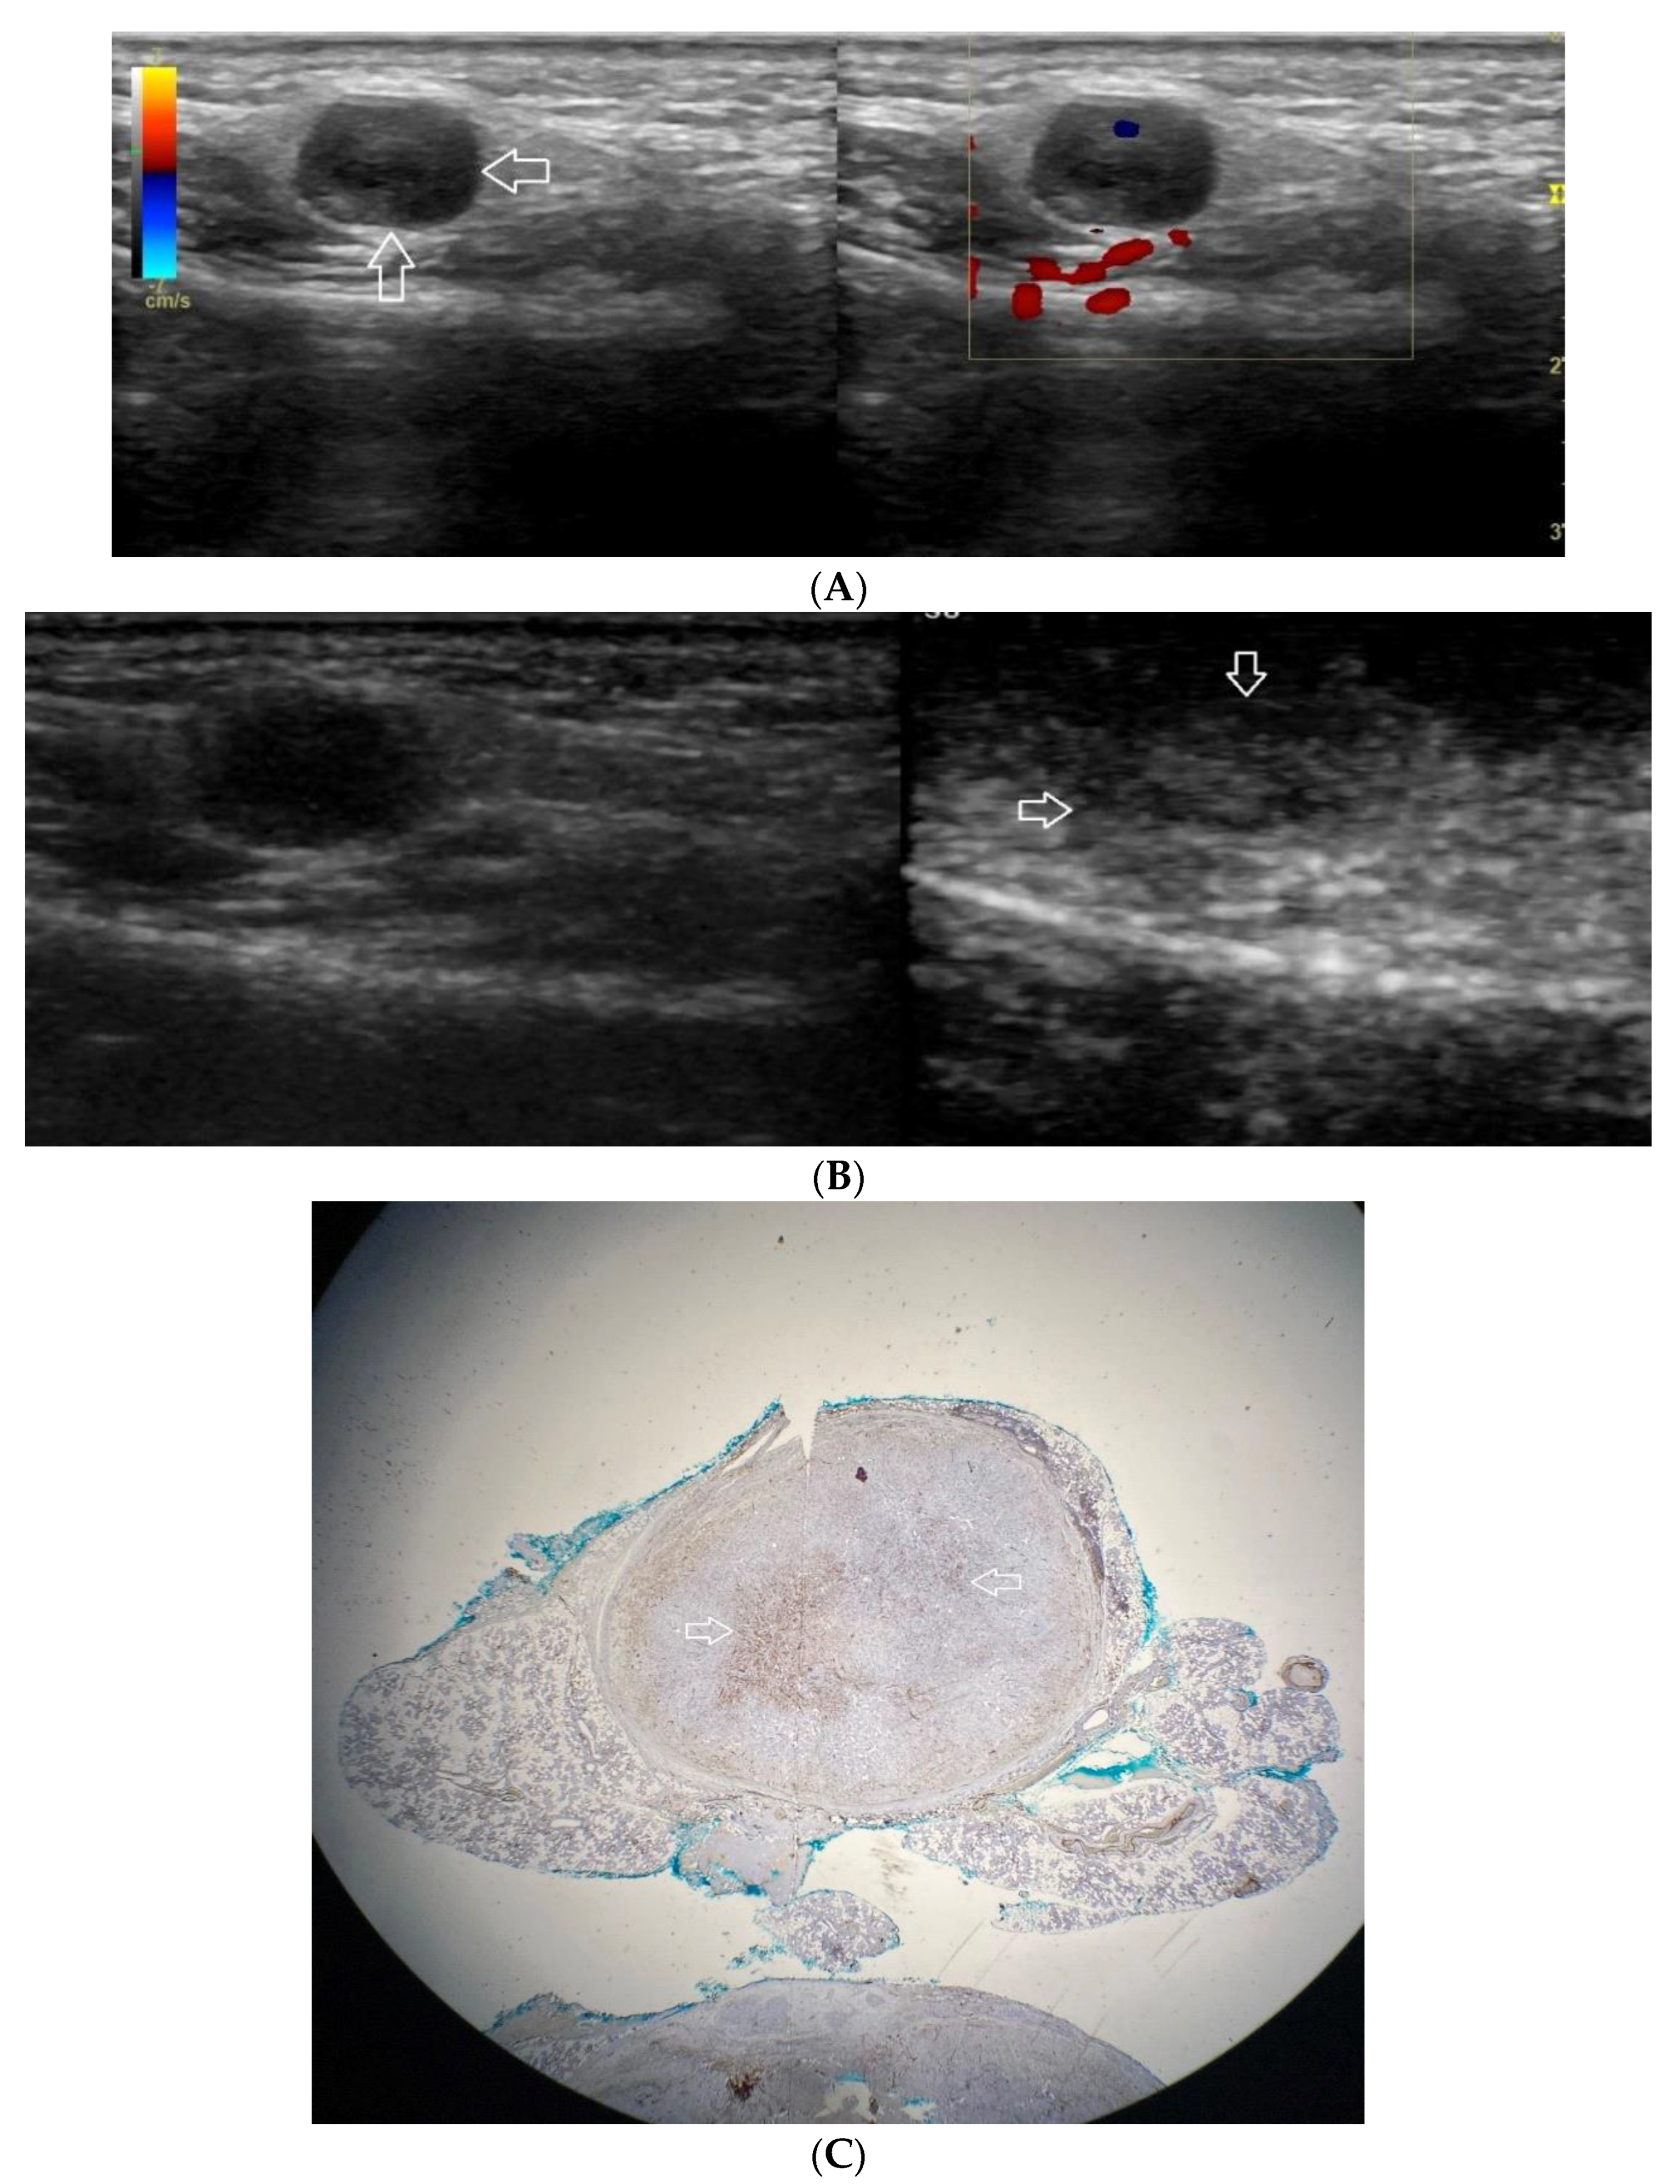

Figure 3.

(A−C) Pleomorphic adenoma. (A) Routine ultrasonographic examination in B presentation and colour Doppler: a small, well-demarcated focal lesion of a homogeneous echostructure. (white arrows). On CD, low blood flow is observed. (B) Contrast-enhanced imaging in arterial phase: a strong homogeneous enhancement of a central part of the lesion. A weakly enhanced peripheral part. (C) Pathomorphological image, immunohistochemistry for CD34. An aggregation of small vessels in central part of the lesion (white arrows).